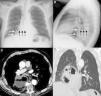

Presentamos el caso de un paciente fumador activo de 73 años sin otros antecedentes de interés que consultó por molestias centrotorácicas y pérdida de peso. Una radiografía de tórax inicial reveló una opacidad retrocardíaca de márgenes bien definidos con un nivel hidroaéreo en su interior, compatible con una hernia de hiato paraesofágica como primera opción diagnóstica, ya que parte del estómago se identificaba en el espacio subfrénico izquierdo (figs. 1A y B). Tres semanas después el paciente consultó por un cuadro autolimitado de hemoptisis; una TC de tórax demostró en ese momento una masa pulmonar extensamente cavitada (figs. 1C y D) con infiltración del mediastino, confirmándose mediante fibrobroncoscopia un carcinoma broncogénico epidermoide.

A) Radiografía posteroanterior de tórax en la que se observa una opacidad en hemitórax derecho (flechas blancas) con un nivel hidroaéreo (flechas negras) en su interior. Nótese la presencia del fundus gástrico (asterisco) en el espacio subfrénico izquierdo. B) Radiografía lateral de tórax en la que se confirma la localización retrocardíaca de la opacidad (flechas blancas) con el nivel hidroaéreo (flechas negras). C) Imagen axial de la TC en la que se identifica una masa extensamente necrótica y cavitada (asterisco) en región paramediastínica del lóbulo inferior derecho. Nótese la presencia de un nivel hidroaéreo en el interior de la cavitación. D) Imagen coronal de la TC (ventana de parénquima pulmonar) en la que se confirma la naturaleza intrapulmonar de la lesión y la integridad de ambos hemidiafragmas.